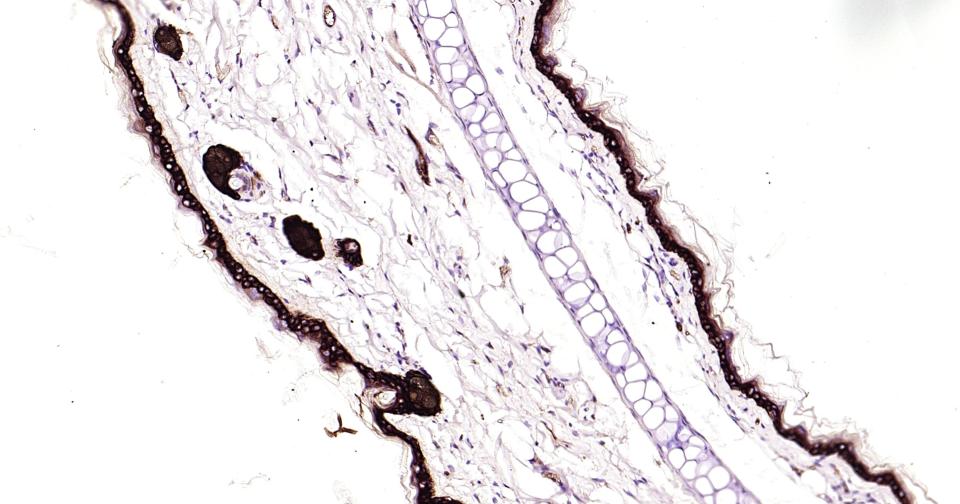

Paraformaldehyde-fixed, paraffin embedded Rat Skin; Antigen retrieval by boiling in sodium citrate buffer (pH6.0) for 15 min; Antibody incubation with Cytokeratin 14? Monoclonal Antibody, Unconjugated(bsm-52054R) at 1:200 overnight at 4°C, followed by conjugation to the bs-0295G-HRP and DAB (C-0010) staining.

Paraformaldehyde-fixed, paraffin embedded Mouse Skin; Antigen retrieval by boiling in sodium citrate buffer (pH6.0) for 15 min; Antibody incubation with Cytokeratin 14? Monoclonal Antibody, Unconjugated(bsm-52054R) at 1:200 overnight at 4°C, followed by conjugation to the bs-0295G-HRP and DAB (C-0010) staining.